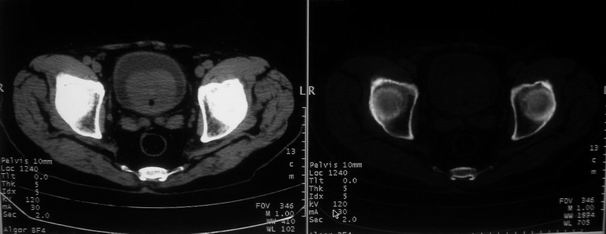

男,85岁,排尿困难。骶椎有问题吗?

前列腺明显增大,突入膀胱,各叶比例协调,密度均匀,精囊腺及精囊角正常;考虑良性增大。

骶骨没有看到明显异常。

这个病人排尿困难应该是前列腺增生造成的,ct对前列腺增生及前列腺癌诊断有一定限度,只能判断前列腺增大,建议还是做一个mr来鉴别一下增生或癌更好,因为增生多发生于中央带,癌多发生于周围带,而mr t2加权图像上中央带和周围带的信号有区别,因此诊断价值更高一些。

1)考虑前列腺增生症并阻塞性膀胱炎。2)骶椎右侧类似囊状骨质密度减低区,边缘骨质硬化,其内为软组织密度影填塞,相邻之骶椎椎管受压变形;考虑为骶椎右侧囊肿或神经纤维瘤。

建议:行mri检查。

1)前列腺明显增大,突入膀胱,各叶比例协调,密度均匀,精囊腺及精囊角正常;考虑前列腺增生症并阻塞性膀胱炎。2)骶椎右侧类似囊状骨质密度减低区,边缘骨质硬化,其内为软组织密度影填塞,相邻之骶椎椎管受压变形;考虑为骶椎右侧囊肿或神经纤维瘤。